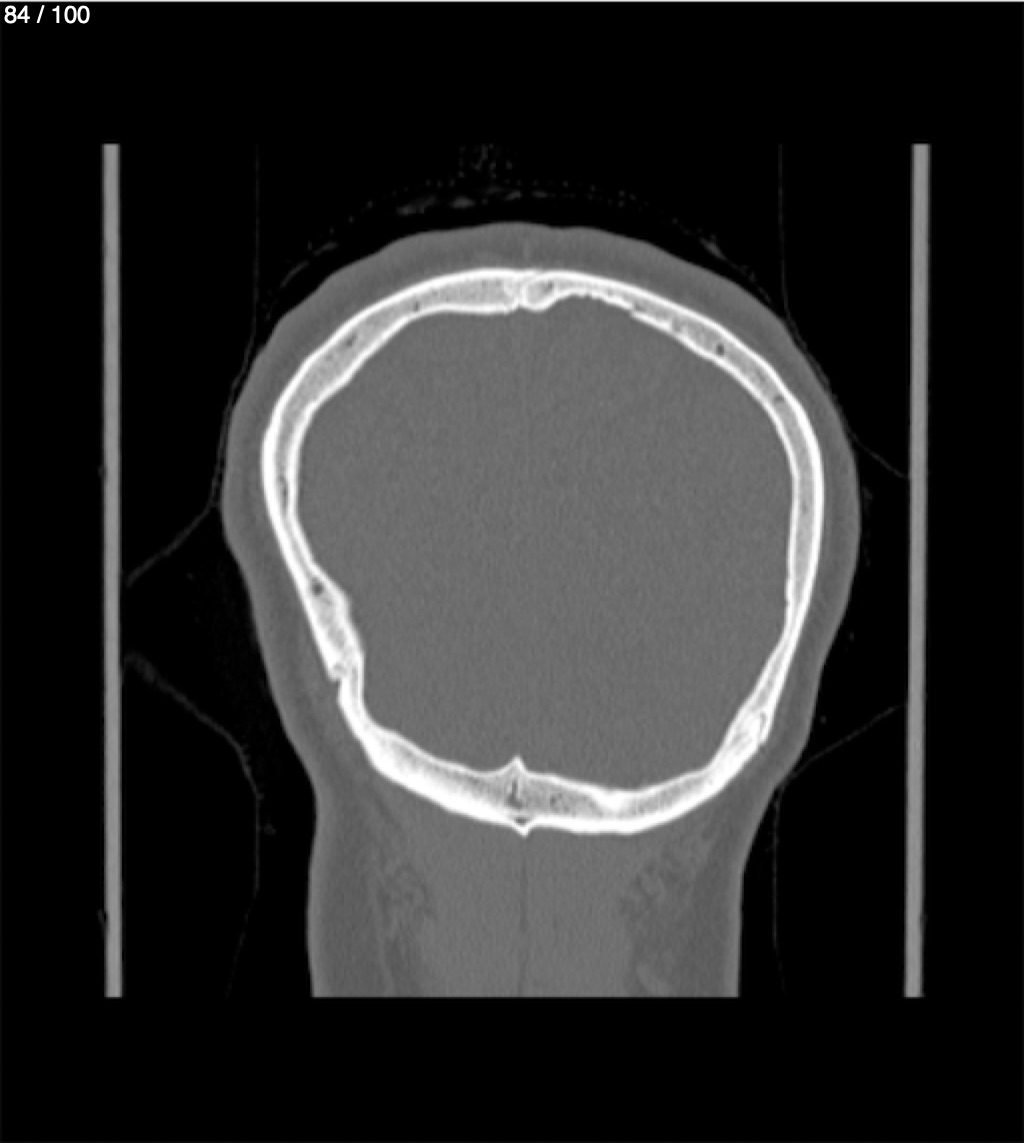

Yonelly Barrios Diaz 35A - T.C Craneo